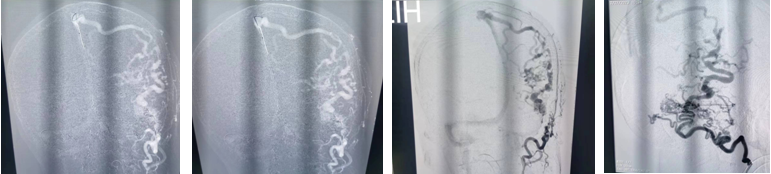

硬脑膜动静脉瘘是严重的脑血管疾病,常见临床症状为头痛,颅内杂音、珠网膜下腔出血、神经功能障碍。该患者系突发头痛入院,经过检查CT发现有蛛网膜下腔出血,DSA检查诊断为硬脑膜动静脉瘘。

手术当天,在麻醉科手术室全力配合下手术顺利开展。王沛医师先进行血管显影,栓塞。术中发现枕动脉有几处分支迂曲,难以通过,进行部分栓塞后转行开颅。开颅设计跨横窦切口,充分暴露横窦上下3cm硬脑膜。幕上剪开硬膜后暴露瘘口及引流静脉。仔细辨别后予以双极电凝烧闭靠近横窦引流静脉及瘘口。幕下烧灼引流静脉,显微剪断除细小引流静脉。整个手术过程顺利,出血控制良好。术毕行DSA检查,杂论血管团消失,脑膜动静脉瘘消失,术后安返病房。目前患者已经清醒,四肢活动正常。